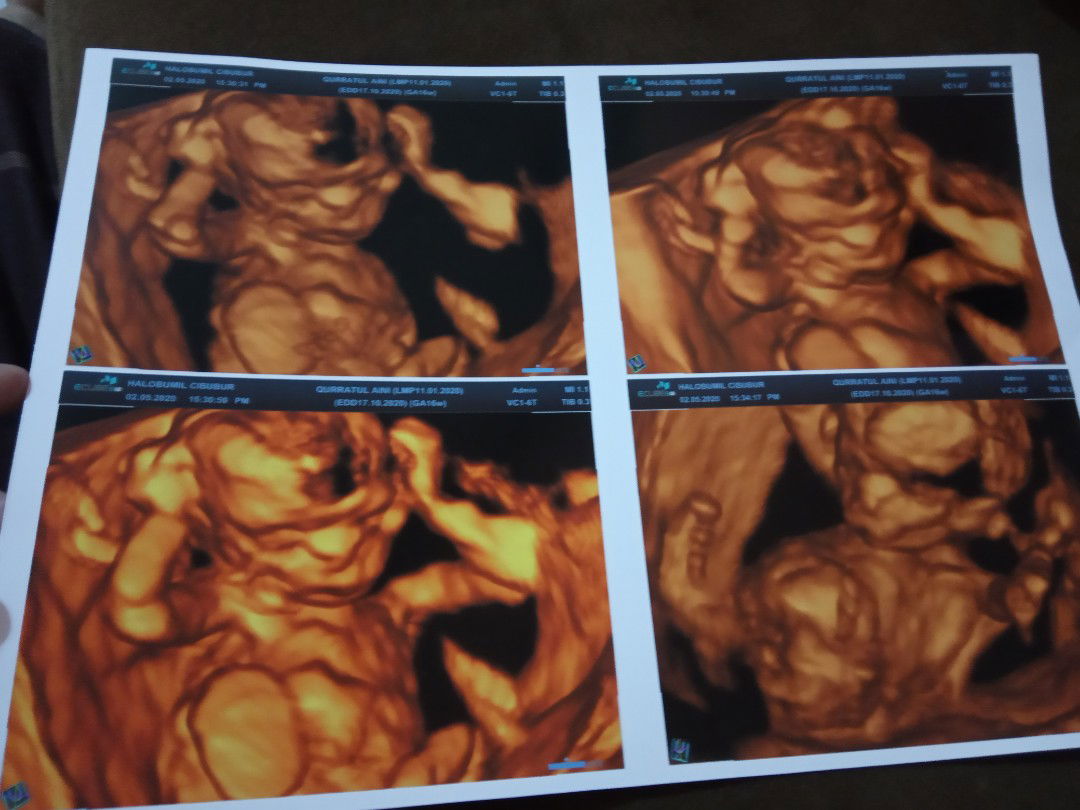

USG 4D 16week

Wkt USG 4D 16week dokter blng JK perempuan. Ini hamil ketiga, 2 kknya cowo semua, baru ini USG 4D happy ya dblng JKnya perempuan, tp ga yakin jg krn msh 16week. Tp dokternya yakin bgt smpi ditulis dibuku periksa JK perempuan. Nunggu next USG msh lama, kira² klo udh USG 4D akurat ga ya hasilnya?